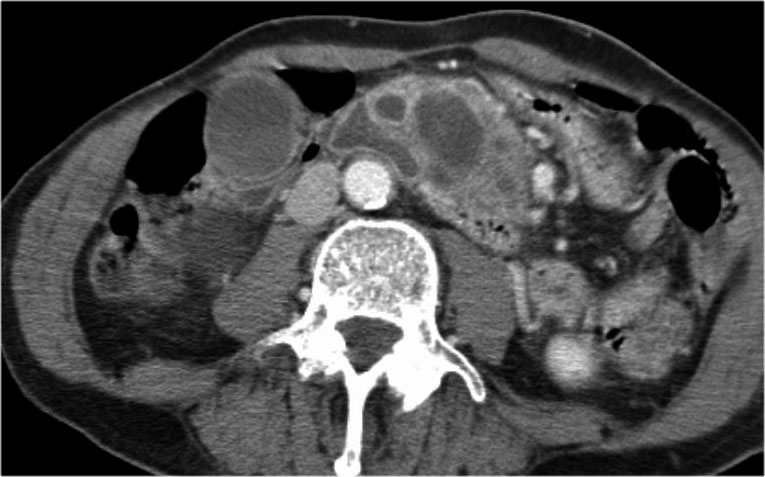

Hình ảnh CT của bệnh nhân nữ 46 tuổi với triệu chứng đau bụng phải mơ hồ.

Các đặc điểm hình ảnh bao gồm:

- Nang có vách ngăn kích thước 7 cm ở đầu tụy.

- Vỏ nang nhẵn.

- Không có thùy hóa (lobulation).

- Không thông với ống tụy chính.

MRI cho thấy nang có vách ngăn ở đầu tụy kích thước 7 cm với vỏ nang nhẵn, không có thùy hóa và không thông với ống tụy chính.

Kết quả phẫu thuật xác nhận u nang tuyến nhầy độ thấp (low grade mucinous cystadenoma) có mô đệm buồng trứng (ovarian stroma).